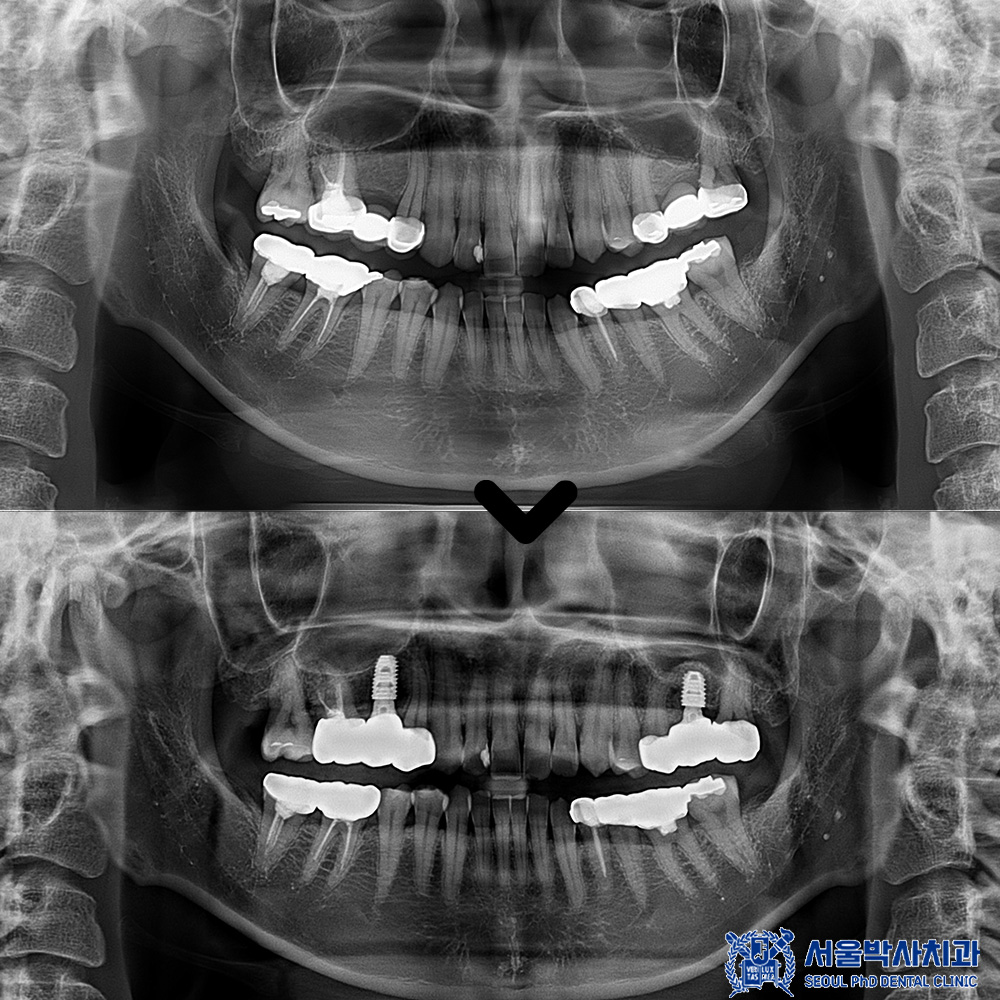

오늘은 기존 브릿지 하방의 충치로 인해

기존 보철 제거 후 크라운과

뼈이식 임플란트를 진행한 사례를

소개해 드리겠습니다.

이후 임플란트가 뼈와

잘 결합된 것이 확인되어,

자연치와 조화를 이루는

최종 보철물을 함께

제작·장착하였습니다.

이를 통해 기능적 회복은 물론,

심미적으로도 자연스러운

결과를 얻을 수 있었습니다.

임플란트의 치유 기간이 충분히 지난 뒤,

보철 작업을 진행했습니다.

정밀한 교합과 잇몸 라인을 구현하기 위해

맞춤형 지대주를 제작하고,

이에 맞는 보철물을 장착하였습니다.

또한 주변 인접 치아들도 함께

크라운 보철을 제작하여

전체적으로 기능과 심미성이

조화를 이루도록 마무리했습니다.